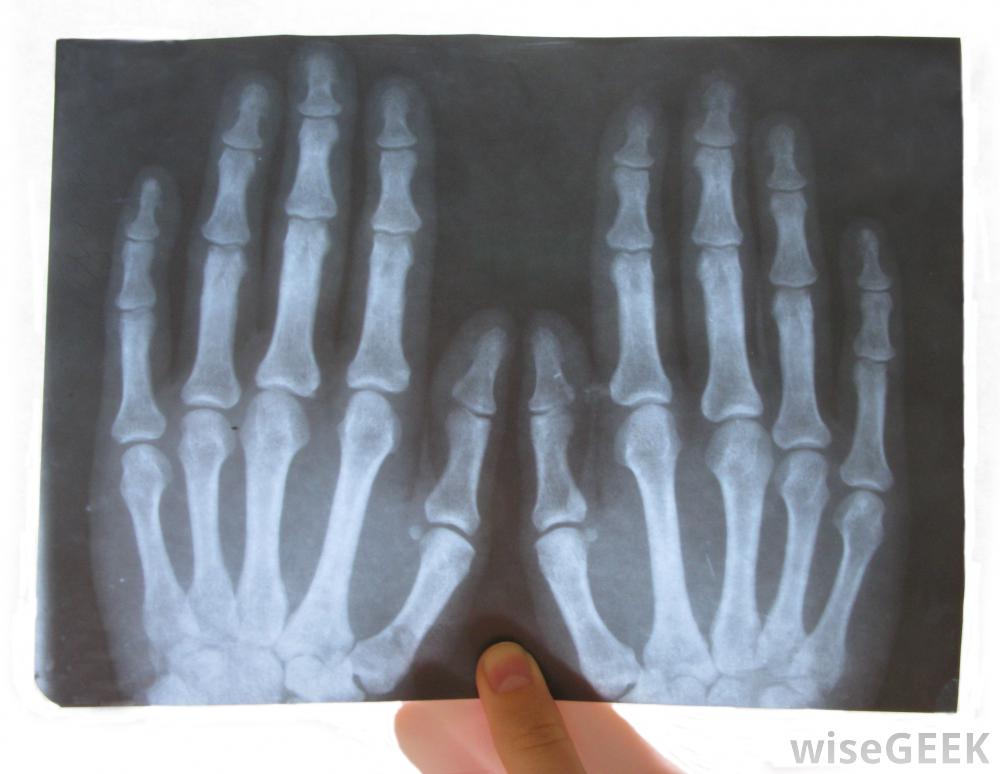

医学成像扫描可用于检查骨骼状况并确保没有造成任何损伤为了检测肢端骨溶解症,医生需要检查手和脚中骨骼的密度。血液测试可以用来确定是否有钙从骨骼中流失。还可以拍X光片和磁共振成像(MRI),这样医生就可以看到是否有对骨骼有任何损伤。

当发现肢端骨溶解症以防止疾病传播时,可能需要截肢在人类,每根手指或脚趾尖的骨头末端都有一个被称为"束"的结构。这些簇状物是骨骼中较宽、较平坦的部分,它们位于被称为远端指骨的骨头末端。在肢端骨溶解症中,这些簇状物分解,导致手指的永久性损伤这种损伤发生缓慢,很难及时诊断和治疗。如果不治疗,骨丢失会导致周围组织死亡。